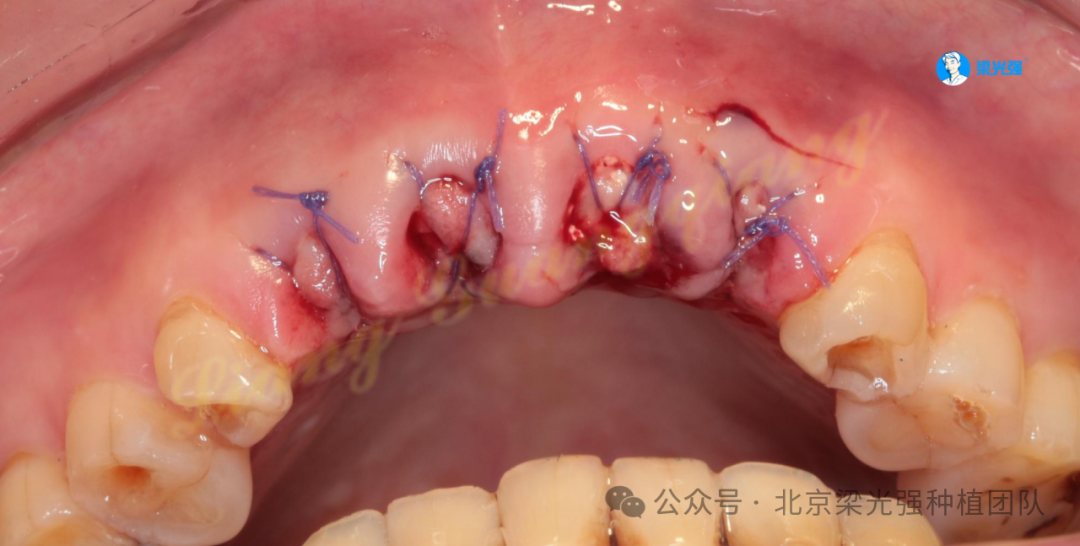

21未植入植体,拔牙窝放了吸收慢的小牛骨,可以长时间维持牙槽骨的丰满度,防止塌陷:

交叉缝合锁住胶原蛋白: